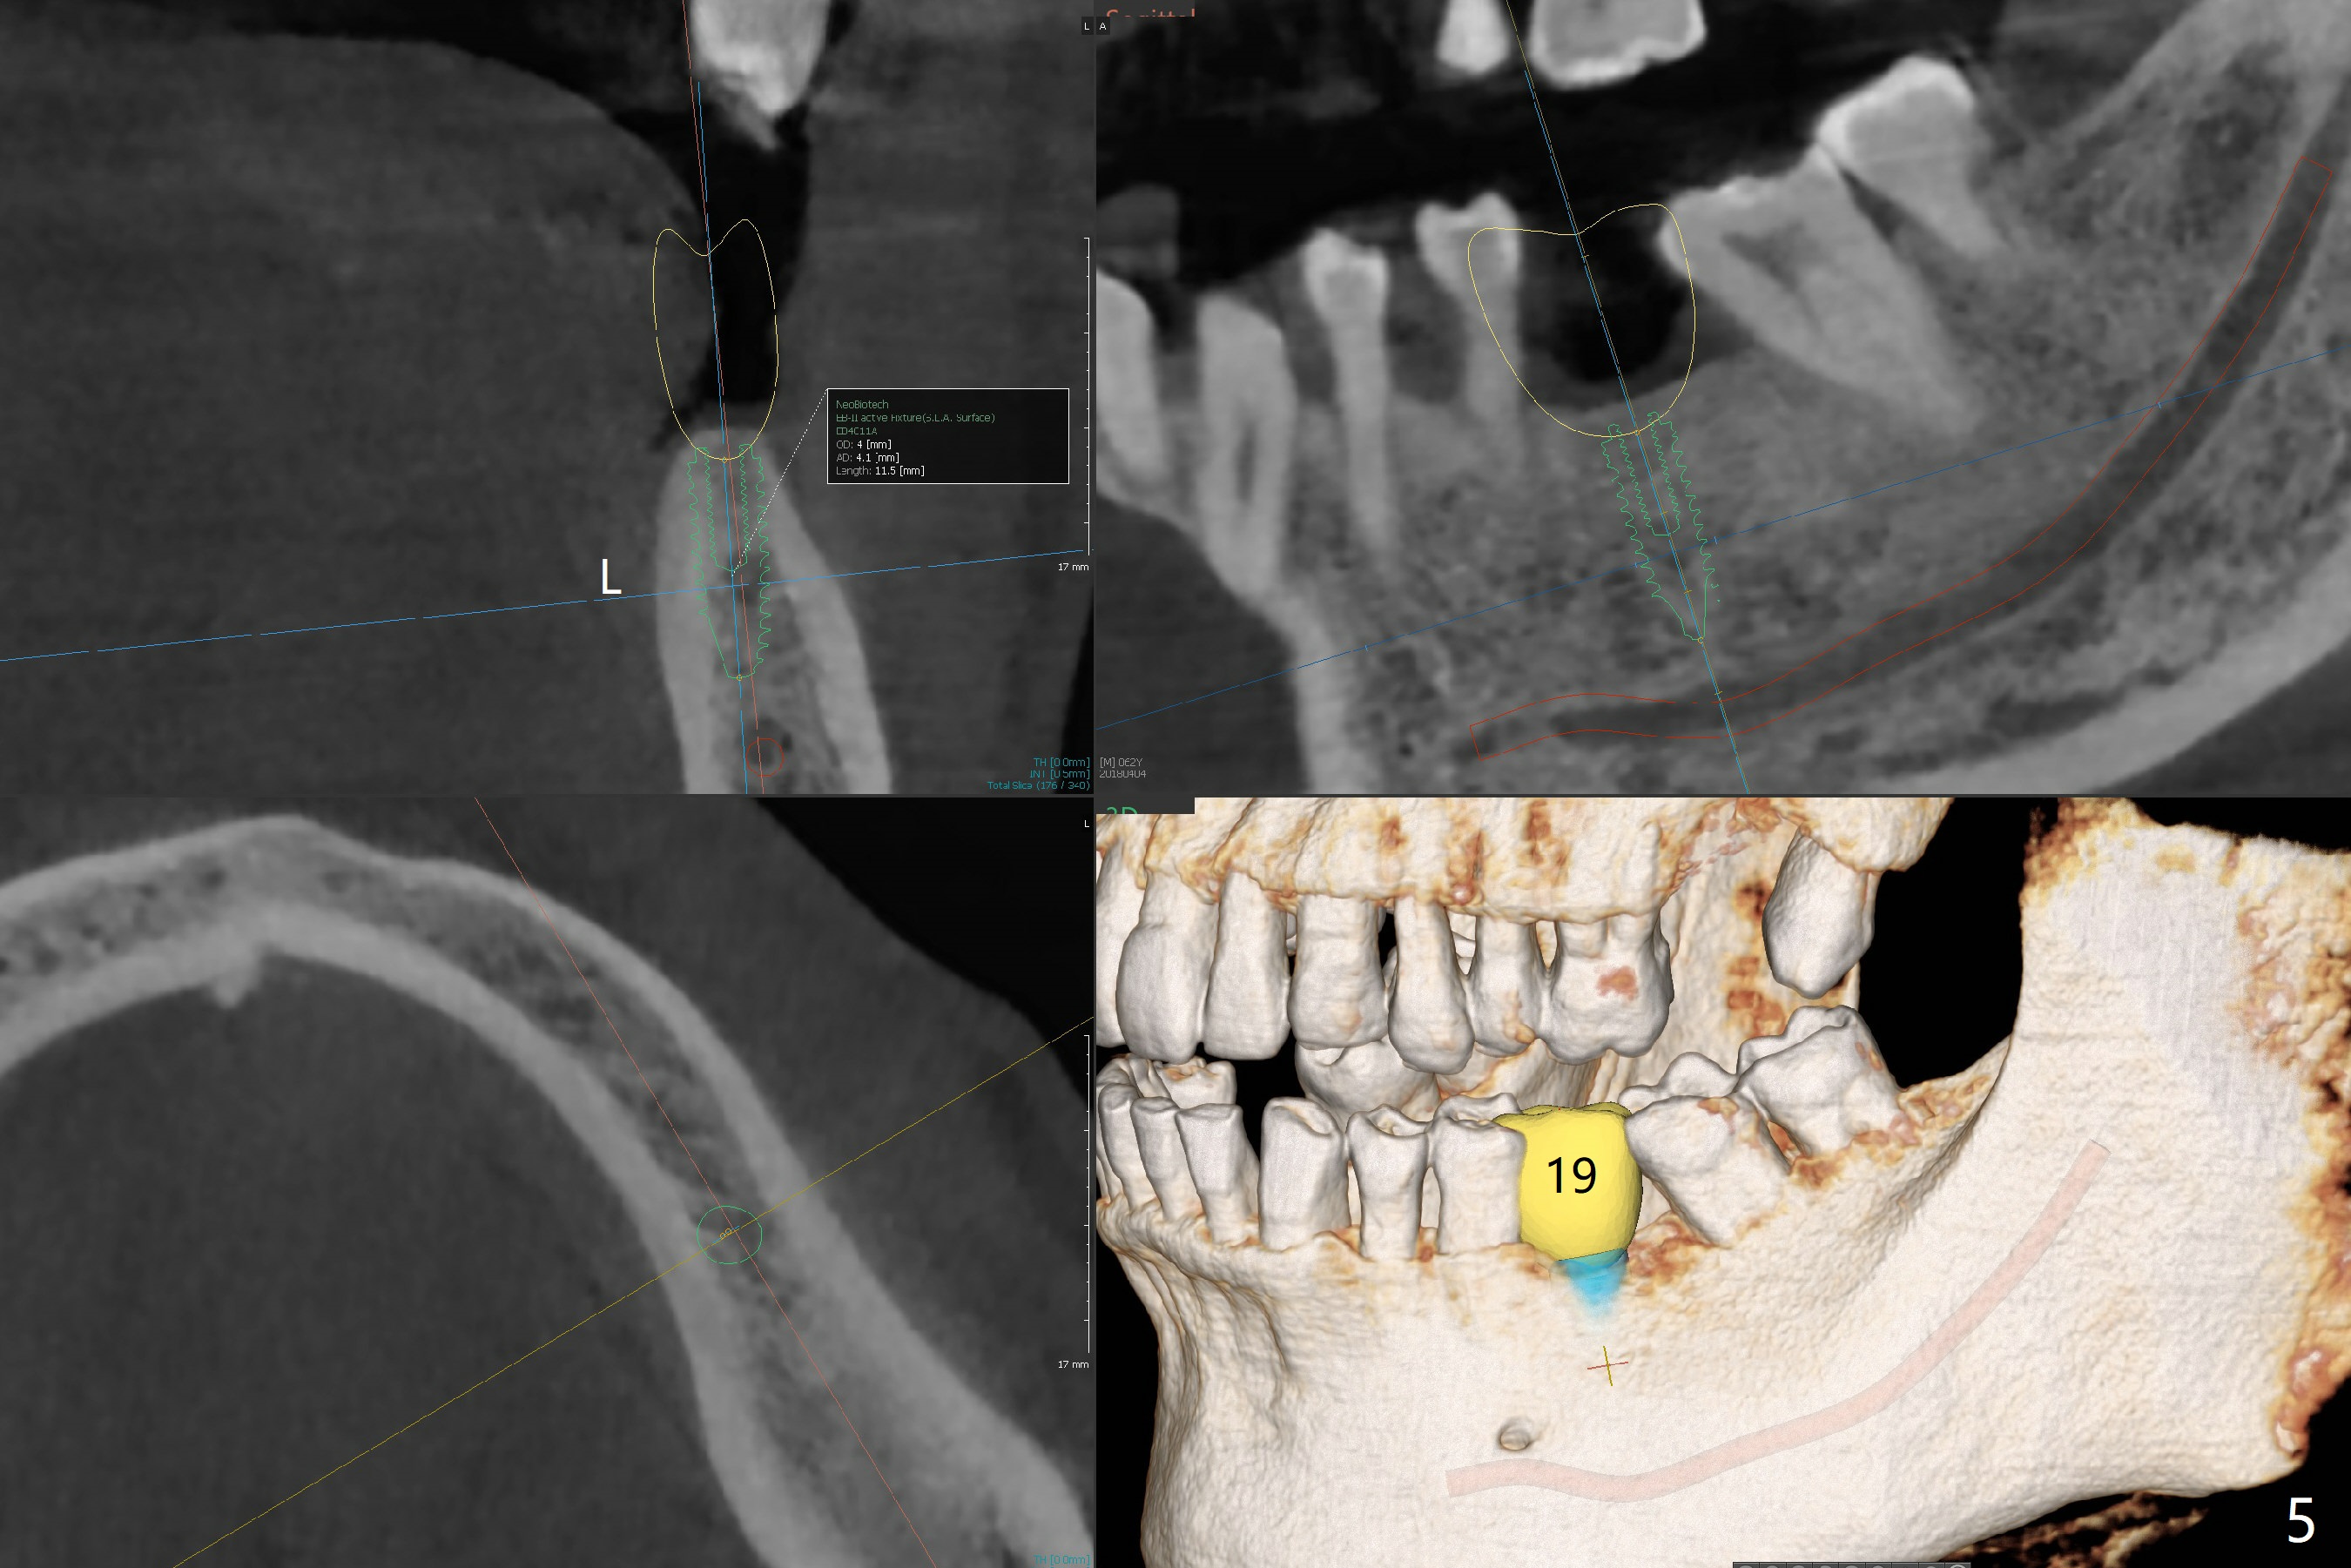

The patient would like to have implants to replace the lower RPD if the 1st surgery turns out to be successful. Due to the presence of the Mental Loop (Fig.1 red dashed line) and thin bone at #29 and 30 (Fig.3,4), 1-piece implants seem to be a good option. A 2-piece implant can be placed at #19 (Fig.5). After cementation of #15 implant crown, reanalysis of CT reveals that a 3x12 mm 1-piece implant is more appropriate at #19 with a space less than a premolar (Fig.6). With 2 of narrow short implants at #29 and 30, violation of the Mental Loop is less likely to happen than a single one in the middle of the edentulous area (Fig.7).